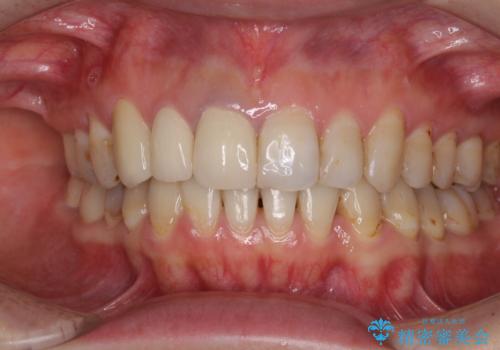

欠損と治療途中の奥歯 インプラント治療と補綴治療

- 下顎左右の奥歯を治療途中で放置してしまっているとのことで来院された患者様です。

欠損部はインプラントによる補綴治療を、土台の外れてしまった歯は、根管治療を行った上で、補綴治療を行うこととしました。

骨格的に下顎が大きく上顎が小さいため、奥歯に力の負担のかかりやすい咬み合わせであるので、治療後は睡眠時にマウスピースを装着することで、セラミッククラウンやインプラント、治療をしたご自身の歯が長持ちするよう指導しています。